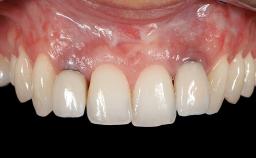

This case demonstrates that a connective-tissue graft in combination with a coronally positioned graft is an effective method of treating cases with peri-implant mucositis and an abutment-level sinus abscess. A 42-year-old man presented with a swelling adjacent to an implant crown at site 21. The swelling had been present for approximately three weeks and was constrained to the buccal and palatal gingival aspects of the implant. A discharge was noted on finger pressure, with localized gingival recession present on the mid- and distolabial aspects of the crown.

Soft Tissue Grafting Staged

Abutment Type CAD/CAM